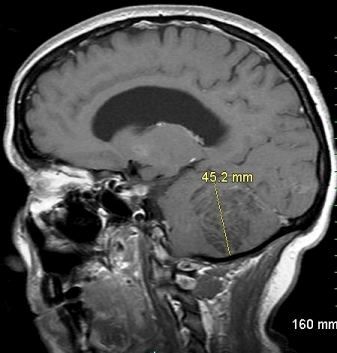

A 39-year-old woman presented with 2-month history of progressively worsening headache and right-sided ataxia. Brain MRI showed a nonenhancing, T1 hypointense mass on the right cerebellar hemisphere, consistent with Lhermitte-Duclos disease.

Image courtesy of Wikrom Warunyuwong, MD, Wisit Cheungpasitporn, MD, Daych Chongnarungsin, MD,

Yasemin S. Tashman, MD, Sirisak Chanprasert, MD.